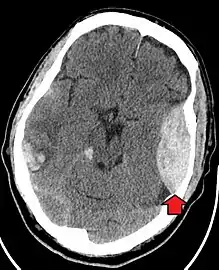

A CT scan showing an epidural hematoma, a variety of intracranial bleeding commonly associated with blunt trauma to the temple region

Traumatic brain injury (TBI)

Traumatic brain injury (TBI) is a significant cause of morbidity and mortality and is most commonly caused by falls, motor vehicle crashes, sports- and work-related injuries, and assaults. It is the most common cause of death in patients under the age of 25. TBI is graded from mild to severe, with greater severity correlating with increased morbidity and mortality.[17][18]

Most patients with more severe traumatic brain injury have of a combination of intracranial injuries, which can include diffuse axonal injury, cerebral contusions, and intracranial bleeding, including subarachnoid hemorrhage, subdural hematoma, epidural hematoma, and intraparenchymal hemorrhage.[8][17] The recovery of brain function following a traumatic injury is highly variable and depends upon the specific intracranial injuries that occur, however there is significant correlation between the severity of the initial insult as well as the level of neurologic function during the initial assessment and the level of lasting neurologic deficits.[17] Initial treatment may be targeted at reducing the intracranial pressure if there is concern for swelling or bleeding within this skull, which may require surgery such as a hemicraniectomy, in which part of the skull is removed.[8][17]